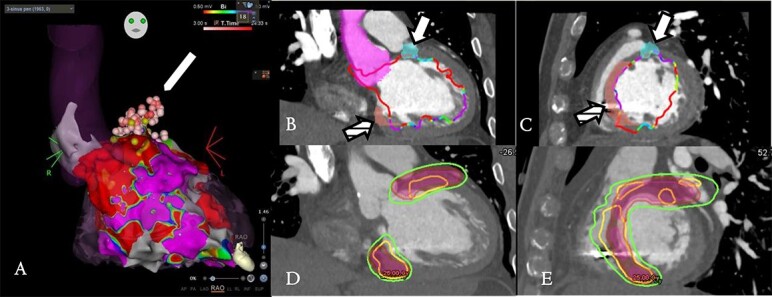

室性心动过速(VT)是一种严重的心律失常,通常采用植入式心律转复除颤器、抗心律失常药物和导管消融术(CA)进行治疗。虽然导管消融术能有效减少复发性 VT,但其对存活率的影响仍不确定,尤其是在有广泛瘢痕的患者中。立体定向心律失常射频消融术(STAR)利用用于癌症治疗的立体定向体放射治疗技术,已成为治疗对 CA 无反应患者 VT 的一种新型疗法。最近的临床试验和病例系列证明了 STAR 的短期疗效和安全性,但长期疗效仍不明确。电解剖图、造影剂增强磁共振成像和核成像等成像技术在治疗规划中起着至关重要的作用,它们能识别 VT 基底面并指导靶点的划分。然而,由于复杂的解剖结构和靶区定义的多变性,挑战依然存在。成像和人工智能的进步有望提高 STAR 的精确度和疗效。STAR 抗心律失常作用的确切机制,包括潜在的纤维化和心脏传导的改善,仍在探索之中。尽管 STAR 潜力巨大,但仍应在前瞻性临床试验中谨慎应用,重点是优化剂量给药和了解长期疗效。有必要开展合作,以规范治疗策略,提高难治性 VT 患者的生活质量。

Ventricular tachycardia (VT) is a severe arrhythmia commonly treated with implantable cardioverter defibrillators, antiarrhythmic drugs and catheter ablation (CA). Although CA is effective in reducing recurrent VT, its impact on survival remains uncertain, especially in patients with extensive scarring. Stereotactic arrhythmia radioablation (STAR) has emerged as a novel treatment for VT in patients unresponsive to CA, leveraging techniques from stereotactic body radiation therapy used in cancer treatments. Recent clinical trials and case series have demonstrated the short-term efficacy and safety of STAR, although long-term outcomes remain unclear. Imaging techniques, such as electroanatomical mapping, contrast-enhanced magnetic resonance imaging and nuclear imaging, play a crucial role in treatment planning by identifying VT substrates and guiding target delineation. However, challenges persist owing to the complex anatomy and variability in target volume definitions. Advances in imaging and artificial intelligence are expected to improve the precision and efficacy of STAR. The exact mechanisms underlying the antiarrhythmic effects of STAR, including potential fibrosis and improvement in cardiac conduction, are still being explored. Despite its potential, STAR should be cautiously applied in prospective clinical trials, with a focus on optimizing dose delivery and understanding long-term outcomes. Collaborative efforts are necessary to standardize treatment strategies and enhance the quality of life for patients with refractory VT.